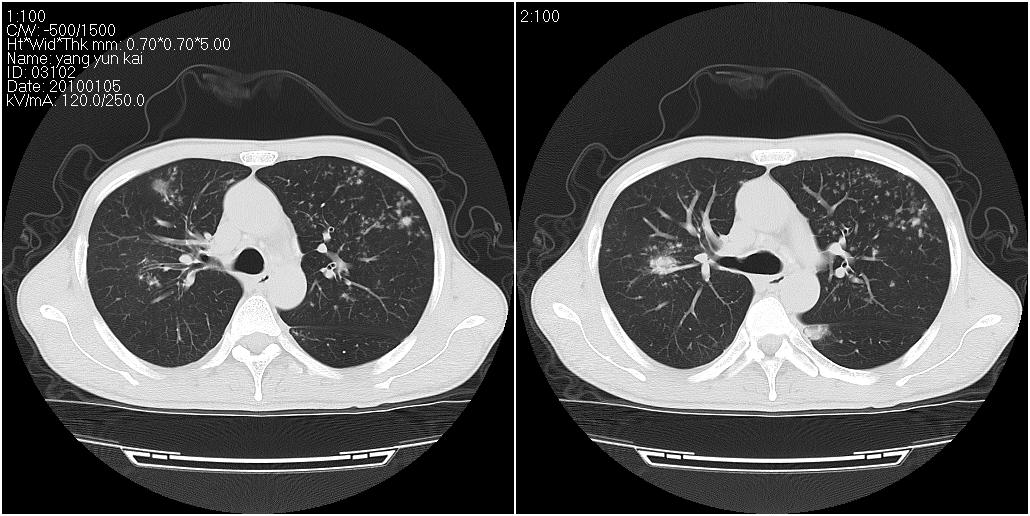

标题: CT23980:男性,47岁。近来咳痰、咳血,血沉增快(40左右),

男性,47岁。近来咳痰、咳血,血沉增快(40左右),痰中未检出结核杆菌。

两肺继发性肺结核并多发性结核球形成,部分病灶内空洞形成。